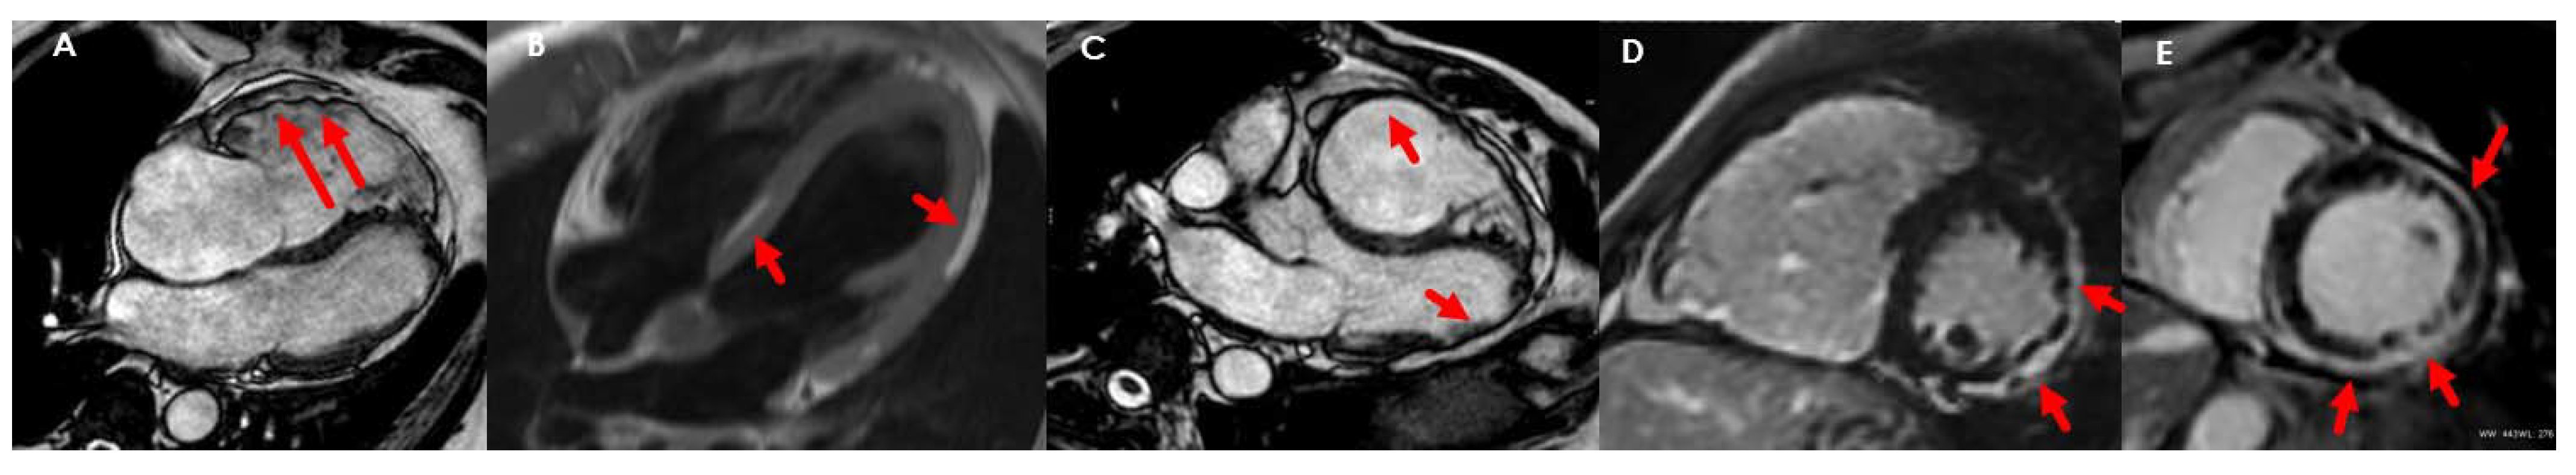

5. Arrhythmogenic Cardiomyopathy

- Marcus, F.I.; McKenna, W.J.; Sherrill, D.; Basso, C.; Bauce, B.; Bluemke, D.A.; Calkins, H.; Corrado, D.; Cox, M.G.; Daubert, J.P.; et al. Diagnosis of arrhythmogenic right ventricular cardiomyopathy/dysplasia: Proposed Modification of the Task Force Criteria. Eur. Heart J. 2010, 121, 1533–1541. [Google Scholar] [CrossRef]

- Corrado, D.; Perazzolo Marra, M.; Zorzi, A.; Beffagna, G.; Cipriani, A.; Lazzari, M.; Migliore, F.; Pilichou, K.; Rampazzo, A.; Rigato, I.; et al. Diagnosis of arrhythmogenic cardiomyopathy: The Padua criteria. Int. J. Cardiol. 2020, 319, 106–114. [Google Scholar] [CrossRef] [PubMed]

- Aquaro, G.D.; De Luca, A.; Cappelletto, C.; Raimondi, F.; Bianco, F.; Botto, N.; Lesizza, P.; Grigoratos, C.; Minati, M.; Dell’Omodarme, M.; et al. Prognostic Value of Magnetic Resonance Phenotype in Patients With Arrhythmogenic Right Ventricular Cardiomyopathy. J. Am. Coll. Cardiol. 2020, 75, 2753–2765. [Google Scholar] [CrossRef] [PubMed]

- Teske, A.J.; Cox, M.G.; Riele, A.T.; De Boeck, B.W.; Doevendans, P.A.; Hauer, R.N.; Cramer, M.J. Early Detection of Regional Functional Abnormalities in Asymptomatic ARVD/C Gene Carriers. J. Am. Soc. Echocardiogr. 2012, 25, 997–1006. [Google Scholar] [CrossRef] [PubMed]

- Saguner, A.M.; Vecchiati, A.; Baldinger, S.H.; Rüeger, S.; Medeiros-Domingo, A.; Mueller-Burri, A.S.; Haegeli, L.M.; Biaggi, P.; Manka, R.; Lüscher, T.F.; et al. Different prognostic value of functional right ventricular parameters in arrhythmogenic right ventricular cardiomyopathy/dysplasia. Circ. Cardiovasc. Imaging 2014, 7, 230–239. [Google Scholar] [CrossRef]

- Sarvari, S.I.; Haugaa, K.H.; Anfinsen, O.-G.; Leren, T.P.; Smiseth, O.A.; Kongsgaard, E.; Amlie, J.P.; Edvardsen, T. Right ventricular mechanical dispersion is related to malignant arrhythmias: A study of patients with arrhythmogenic right ventricular cardiomyopathy and subclinical right ventricular dysfunction. Eur. Heart J. 2011, 32, 1089–1096. [Google Scholar] [CrossRef] [Green Version]

- Pinamonti, B.; Dragos, A.M.; Pyxaras, S.A.; Merlo, M.; Pivetta, A.; Barbati, G.; Di Lenarda, A.; Morgera, T.; Mestroni, L.; Sinagra, G. Prognostic predictors in arrhythmogenic right ventricular cardiomyopathy: Results from a 10-year registry. Eur. Heart J. 2011, 32, 1105–1113. [Google Scholar] [CrossRef] [PubMed]